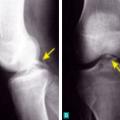

Lésions osseuses radiologiques d'une rupture du ligament croisé antérieur

LESIONS PERI-ARTICULAIRES

LESIONS LIGAMENTAIRES

Lésion méniscale médiale traumatique verticale de grade 3